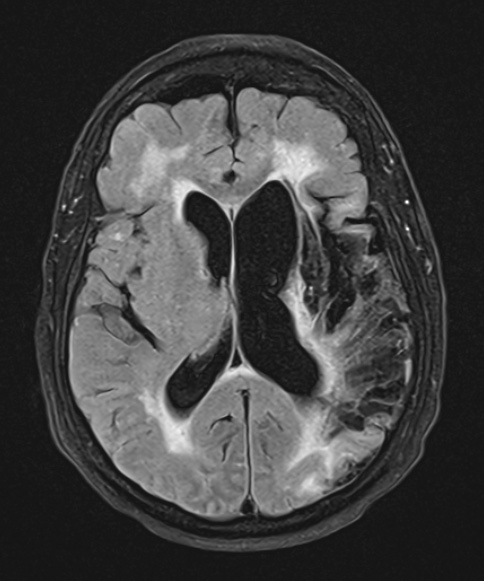

The extent of left MCA infarction and periventricular hyperintensities are shown in this FLAIR MRI Scan.